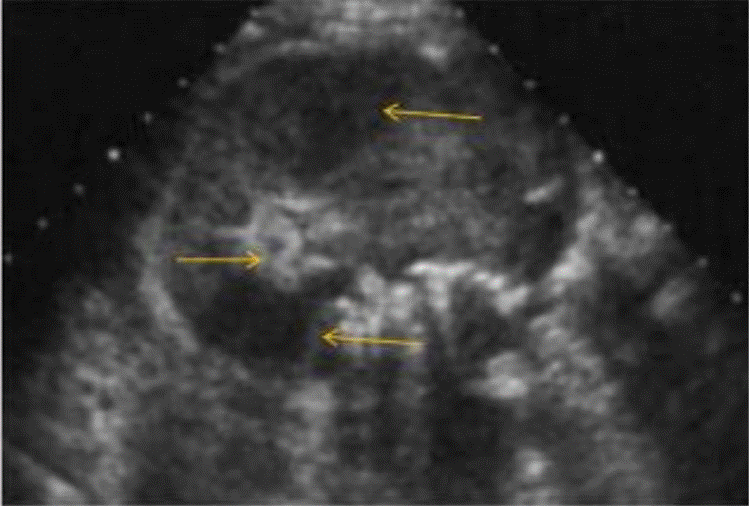

La ecografía abdominal total mostró hallazgos sugestivos de PNE izquierda (Figura 1), por lo que se solicitó valoración por urología; este servicio indicó continuar con la misma terapia antibiótica y realizar UROTAC que mostró microlitiasis renal bilateral, litiasis ureteral izquierda y proceso infeccioso inflamatorio con presencia de gas en el riñón izquierdo, lo que indicó diagnóstico de PNE izquierda tipo 2 (Figuras 2 y 3). Ante los hallazgos radiológicos y el reporte de urocultivo positivo para Escherichia coli multisensible, se decidió hacer rotación de cubrimiento antibiótico a carbapenémicos debido al alto riesgo de mortalidad.